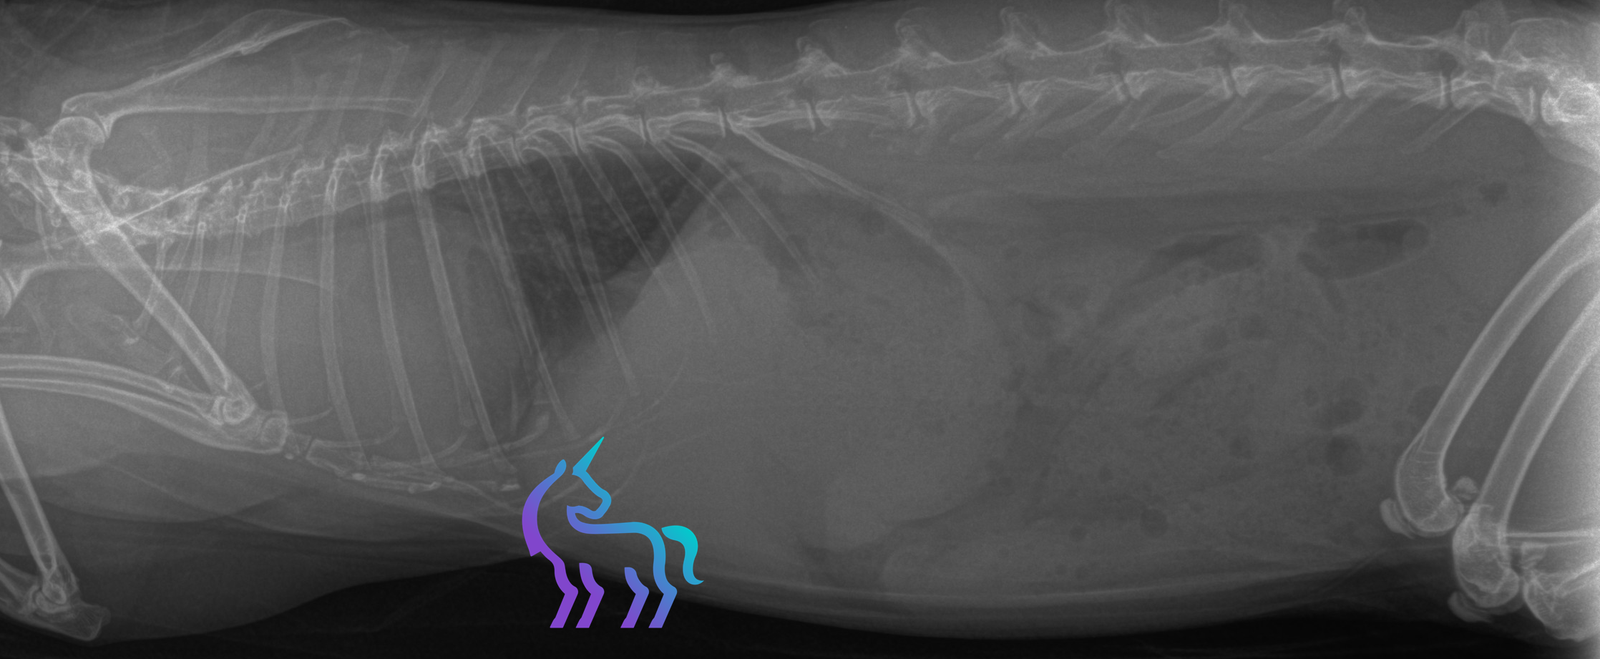

Imagerie thoracique

- Radiographies thoraciques : mise en évidence d’une masse médiastinale craniale, parfois associée à une déviation de la trachée ou à des modifications pulmonaires secondaires.